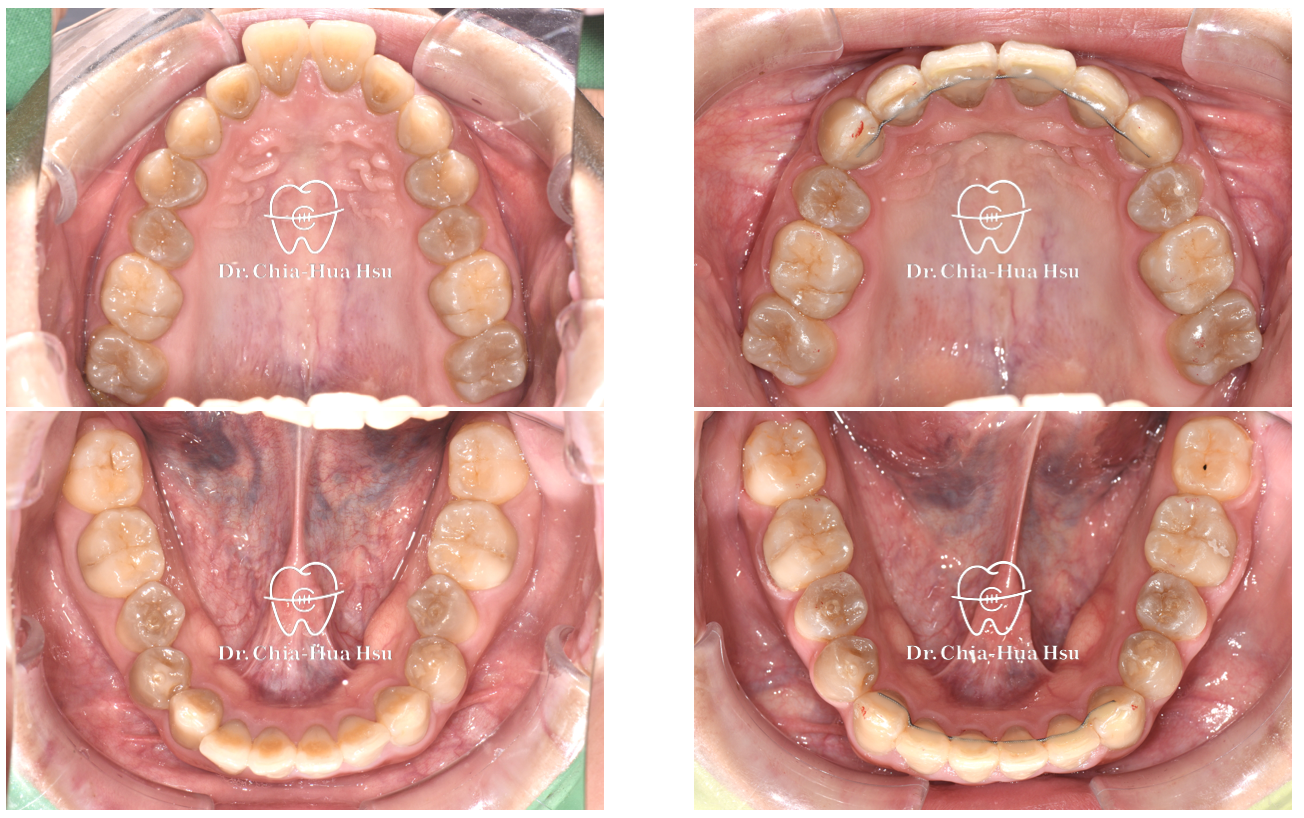

• 問題分析:患者是牙齒二類咬合(Skeletal Class II)、方臉型、暴牙以及齒列不整齊。

• 治療方式:使用傳統金屬矯正器,考量到患者臉型不適合退太多,因此只拔除上顆兩顆小臼齒以及兩支暫時性迷你骨釘來完成治療。

治療前